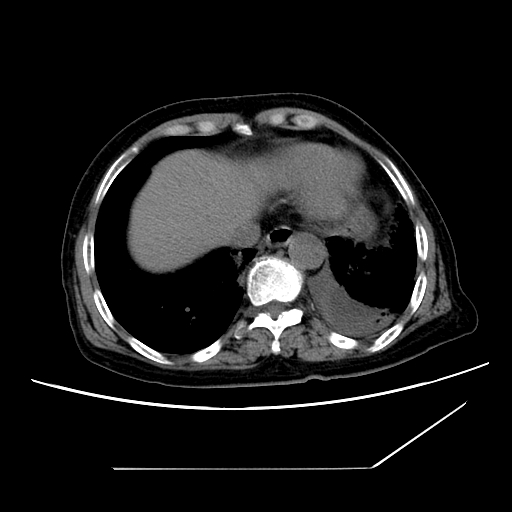

标题: CT25393:病人45岁,咳嗽,吐黄痰带血丝,发热,胸闷月余 [打印本页]

标题: CT25393:病人45岁,咳嗽,吐黄痰带血丝,发热,胸闷月余

1、左肺中央型肺癌并双肺弥漫性转移   2、双肺部感染    3、肺大泡     4、左侧胸腔积液

双侧肺弥漫性病变,可见“空泡征”及“蜂窝征”,考虑肺泡癌可能性大,左侧胸腔积液,考虑胸膜受累可能!

1)不排除肺泡癌可能。2)左侧胸腔积液。